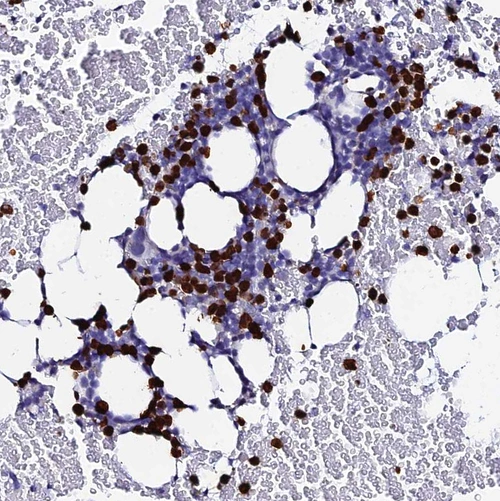

Immunohistochemical staining of human bone marrow shows strong nuclear positivity in hematopoietic cells.